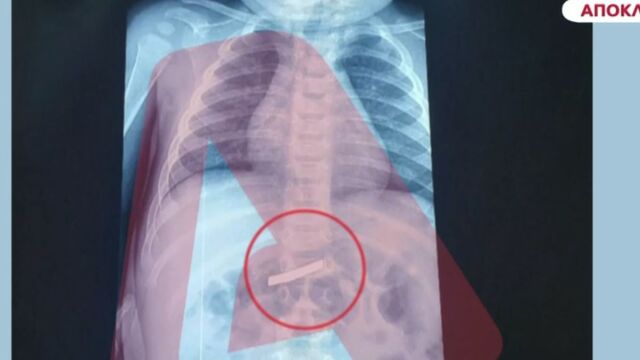

Απίστευτο περιστατικό στο Νοσοκομείο Παίδων: Τρίχρονος κατάπιε ξυράφι - Υποβλήθηκε σε χειρουργείο (Βίντεο)

Στο νοσοκομείο Παίδων μεταφέρθηκε ένας 3χρονος από τους γονείς του, επειδή κατάπιε ξυράφι. Το παιδί χειρουργήθηκε και πλέον δεν διατρέχει κάποιον κίνδυνο